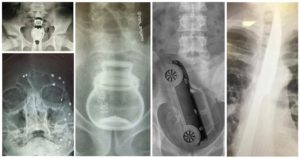

- рентгеноскопию органов желудочно-кишечного тракта;

При рентгенологическом исследовании выявляют плотную тень контрастного инородного тела (чаще в правом бронхе), при обтурационном ателектазе в результате полной закупорки бронха – снижение прозрачности легочного поля, высокое стояние купола диафрагмы, сужение межреберных промежутков, эмфизему другого легкого, смещение тени средостения в сторону пораженного бронха.

При неполной закупорке бронха на стороне поражения отмечают ограничение подвижности купола диафрагмы, снижение прозрачности легочного поля, смещение тени средостения в пораженную сторону при вдохе (симптом Гольцкнехт-Якобсона).

При клапанной (вентильной) закупорке бронха прозрачность легкого на стороне поражения повышается (эмфизема), межреберные промежутки расширяются, купол диафрагмы опускается, ее экскурсии ограничиваются, тень средостения смещается в здоровую сторону.